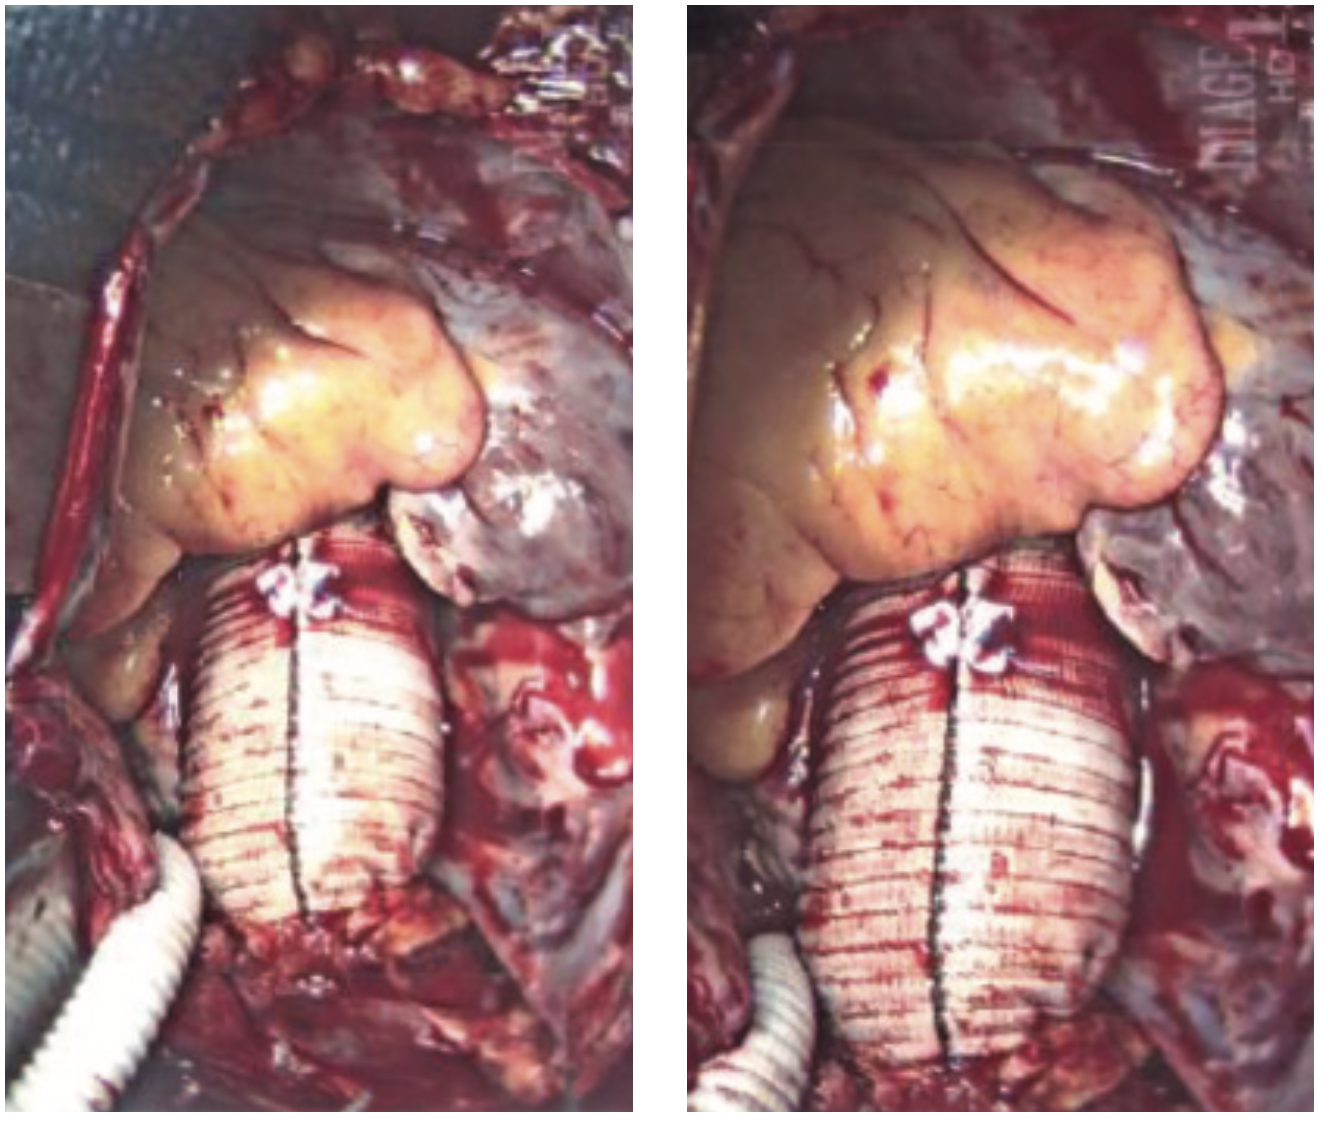

She was widowed, lived alone, and quit smoking 4 years ago, with a 40 pack-year smoking history. Her family history was non-contributory. She had noticed some dyspnea on exertion during routine chores such as mowing the lawn and carrying laundry upstairs, which she attributed to deconditioning. She was otherwise asymptomatic, even during her episode of supraventricular tachycardia (SVT) during her recent colonoscopy. During her TTE, the technologist notified the cardiologist of a 9-centimeter ascending aortic aneurysm, effacing the sinotubular junction with dilated sinuses of Valsalva. The TTE also demonstrated moderate aortic regurgitation. There was no evidence of vegetation or aortic dissection, or pericardial effusion. The patient was admitted to the University Hospital from the office for further management. A computed tomography scan of the chest with contrast was done in the emergency department to further define the aneurysm. Cardiac catheterization was performed the following day, revealing normal coronaries, normal left ventricular systolic function, and a 9-centimeter ascending aortic aneurysm. She underwent urgent cardiothoracic surgery. The surgeon repaired her aortic root with a Dacron patch and replaced her aortic valve with a bioprosthetic pericardial aortic valve. The patient had an otherwise unremarkable post-operative course, primarily consisting of blood pressure control. She was discharged with surgical follow-up within 1 week and cardiology follow-up in 2 weeks.

Thoracic aortic aneurysms are usually approached with surgical repair using a cardiopulmonary bypass and an aortic root replacement.4 Basic principles of a TAA repair are to sew to healthy tissue, replacing the aortic arch if there is no pathology, extending the hemi-arch replacement of the proximal arch if it is involved, and total arch replacement if the entire arch is aneurysmal.7 Aortic grafts made of Dacron are used due to their tensile strength and rate of tissue ingrowth.7 The post-operative course and follow-up are dependent upon any surgical complications and patient comorbidities. Hospitalization for TAA repair is between 7 to 10 days, although this is dependent on post-surgical complications.7 Follow-up imaging is performed at 1, 3, 6, and 12-month intervals.7 Afterwards, if the aorta is stable, only yearly imaging is needed.